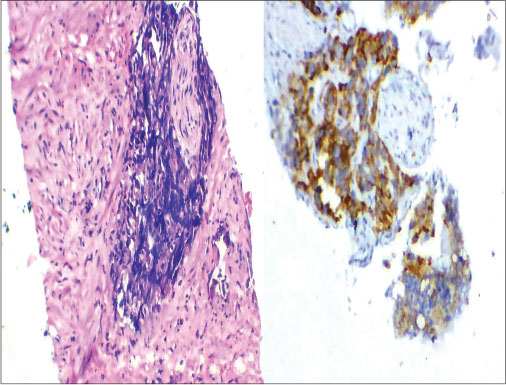

| Figure 4 Photomicrograph showing prostatic adenocarcinoma – Gleason Grade 3 (H and E, ×400), (b) Photomicrograph showing prostatic adenocarcinoma – GleasonGrade 4 (H and E, ×400), (c) Photomicrograph showing prostatic adenocarcinoma – Gleason Grade 5 (H and E, ×400), (d) Androgen receptor nuclear positivity of malignant epithelial cells (×400), (e) Androgen receptor positivity of stromal cells (×400), (f) human epidermal growth factor receptor 2/neu membrane positivity of malignant epithelial cells (×400)

On all the 38 cases, AR staining was done. The percentage of staining of AR in adjacent benign areas ranged from 74% to 89% with the mean of 82.84%, and in malignant areas, it ranged from 76% to 99% with the mean of 89.16%, thus showing an increase in the percentage of staining of malignant areas [Figure 4] in comparison to the adjacent benign glandular structure [Figure 6]. The two-tailed P < 0>

On 38 malignant cases, HER2/neu staining was done [Figure 4] and [7]. Overexpression and negative expression of HER2/neu was compared with respect to age, Gleason score, and the PSA value [Figure 8]. In this study, it was found that younger prostatic cancer patient (<60>10 showed overexpression of HER2/neu.

| Figure 7 Photomicrograph showing perineural invasion (H and E, ×400) (b) Photomicrograph showing human epidermal growth factor receptor 2/neu membrane positivity of malignant epithelial cells (×400)